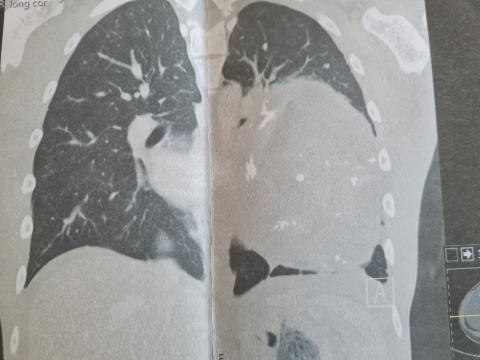

De tumor in de borstholte

Dit is een foto van de tumor in de borstholte voor de operatie. Beiden kanten zouden hier donker grijs moeten zijn maar rechts zie je een lichte grijze bol zitten die daar niet thuis hoort. We hopen natuurlijk snel een nieuwe foto te krijgen waarop deze bol inderdaad weg is.